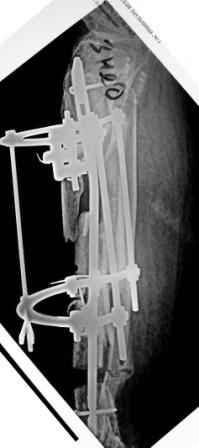

1) Наложить Аппарат Илизарова. В аппарате восстановить оси трех смещенных относительно друг-друга фрагментов большеберцовой кости. Устранить вальгусную деформацию дистального отдела большеберцовой кости.

Что и было выполнено.

- Была выполнена репозиция в аппарате (рис1)